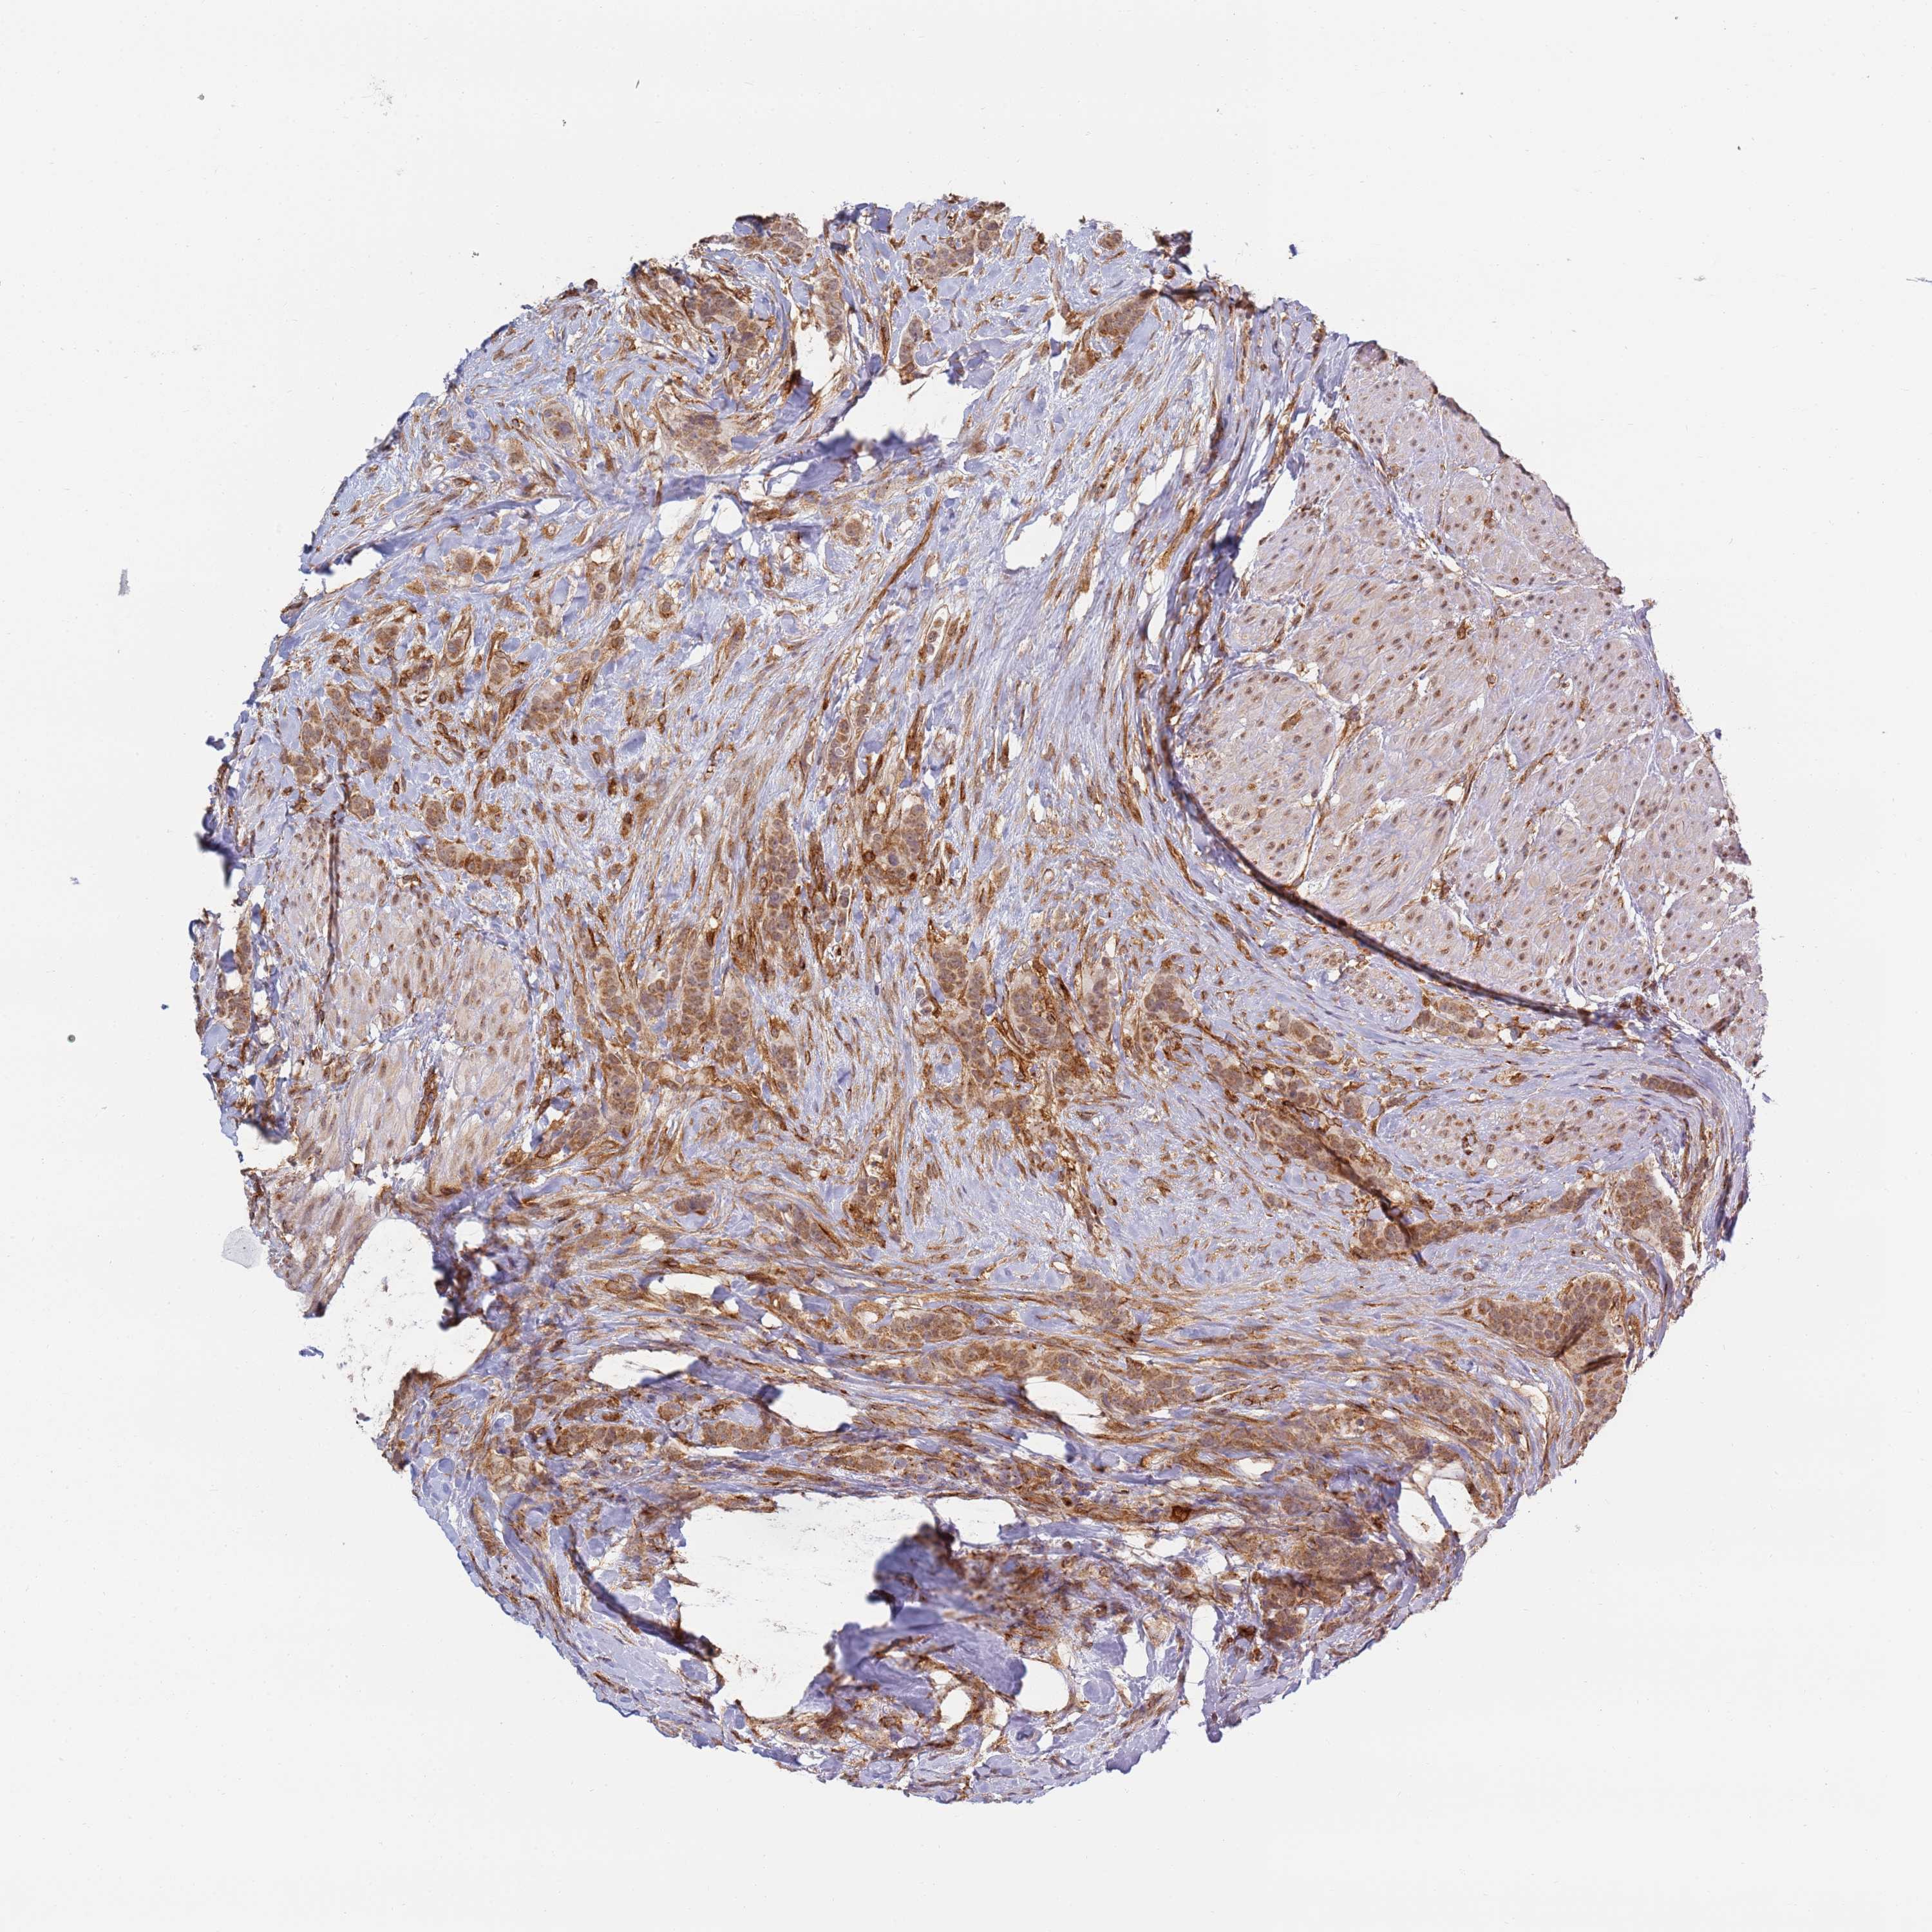

CANCER BREAST CANCER Show tissue menu

BRCA TCGA BRCA VALIDATION PROTEIN EXPRESSION

Breast cancer

Human cancer